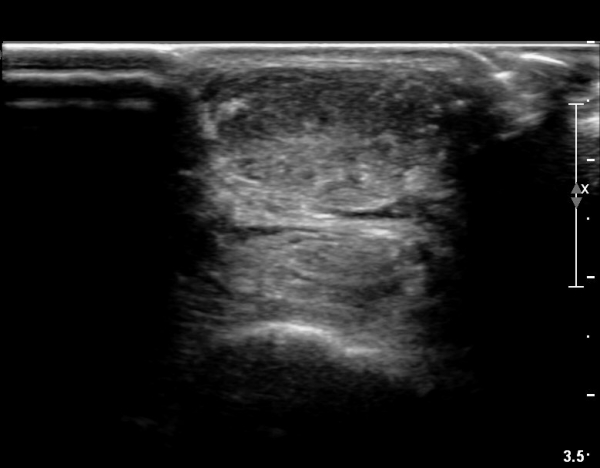

³»Ãø ºñº¹±Ù Á¾´Ü¸é°Ë»ç¿¡¼­ ³»Ãø ¹èº¹±Ù ¸»´ÜºÎ ÆÄ¿­°ú °¡Àڹ̱٠½ÉºÎ¿¡ ¼ö¾×Àú·ù°¡ °üÂûµÊ(»çÁø 1, 2).

¾ÆÅ³·¹½º°Ç Á¾´Ü¸é°Ë»ç¿¡¼­ ¾ÆÅ³·¹½º°Ç ¸»´ÜºÎ¿¡ ¾ÆÅ³·¹½º°ÇÀÇ Àú¿¡ÄÚºÎÁ¾, ±¹¼ÒÀû ¿¬°á¼º ¼Ò½Ç,